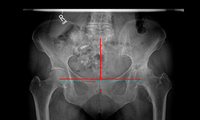

Eine neue Funktion der Version 4 von Hectec mediCAD ist die Spiegelung des Hüftgelenkmittelpunkts.Die neue Version der präoperativen Planungssoftware mediCAD…